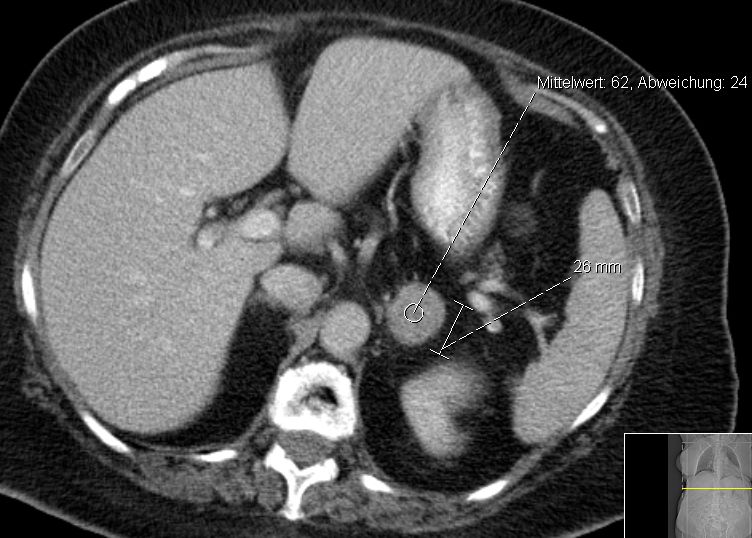

79-jähriger berenteter, adipöser Fleischer mit respiratorischer Insuffizienz. Urothel-Ca vor 15 Jahren. Jetzt kleines Bronchial-Karzinom. Beim Tumorstaging wurde ein großer NN-Tumor rechts entdeckt. | |||

![]() |